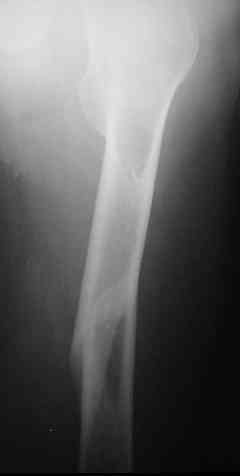

Уважаемые коллеги,пару дней назад к нам поступил пациент 54 лет с таким вот переломом правого бедра. Сейчас на скелетном вытяжении. Хотелось бы услышать мнения по поводу природы округлого просветления в подвербельной области (аневризмальная киста?)и тактики лечения.

Dear all, a few days ago a 54 y.o. patient was admitted to our hospital with this fracture of the right femur. Now he is on a skeletal traction. I'd appreciate your opinion as to: 1.the nature of a lucent lesion (?) in subtrochanteric area - is it ABC? 2.treatment options.Thanks, Peter Romchuk, Central City Hospital, Rivne, Ukraine.С уважением, Петр Ромчук, ЦГБ г.Ривне, Украина